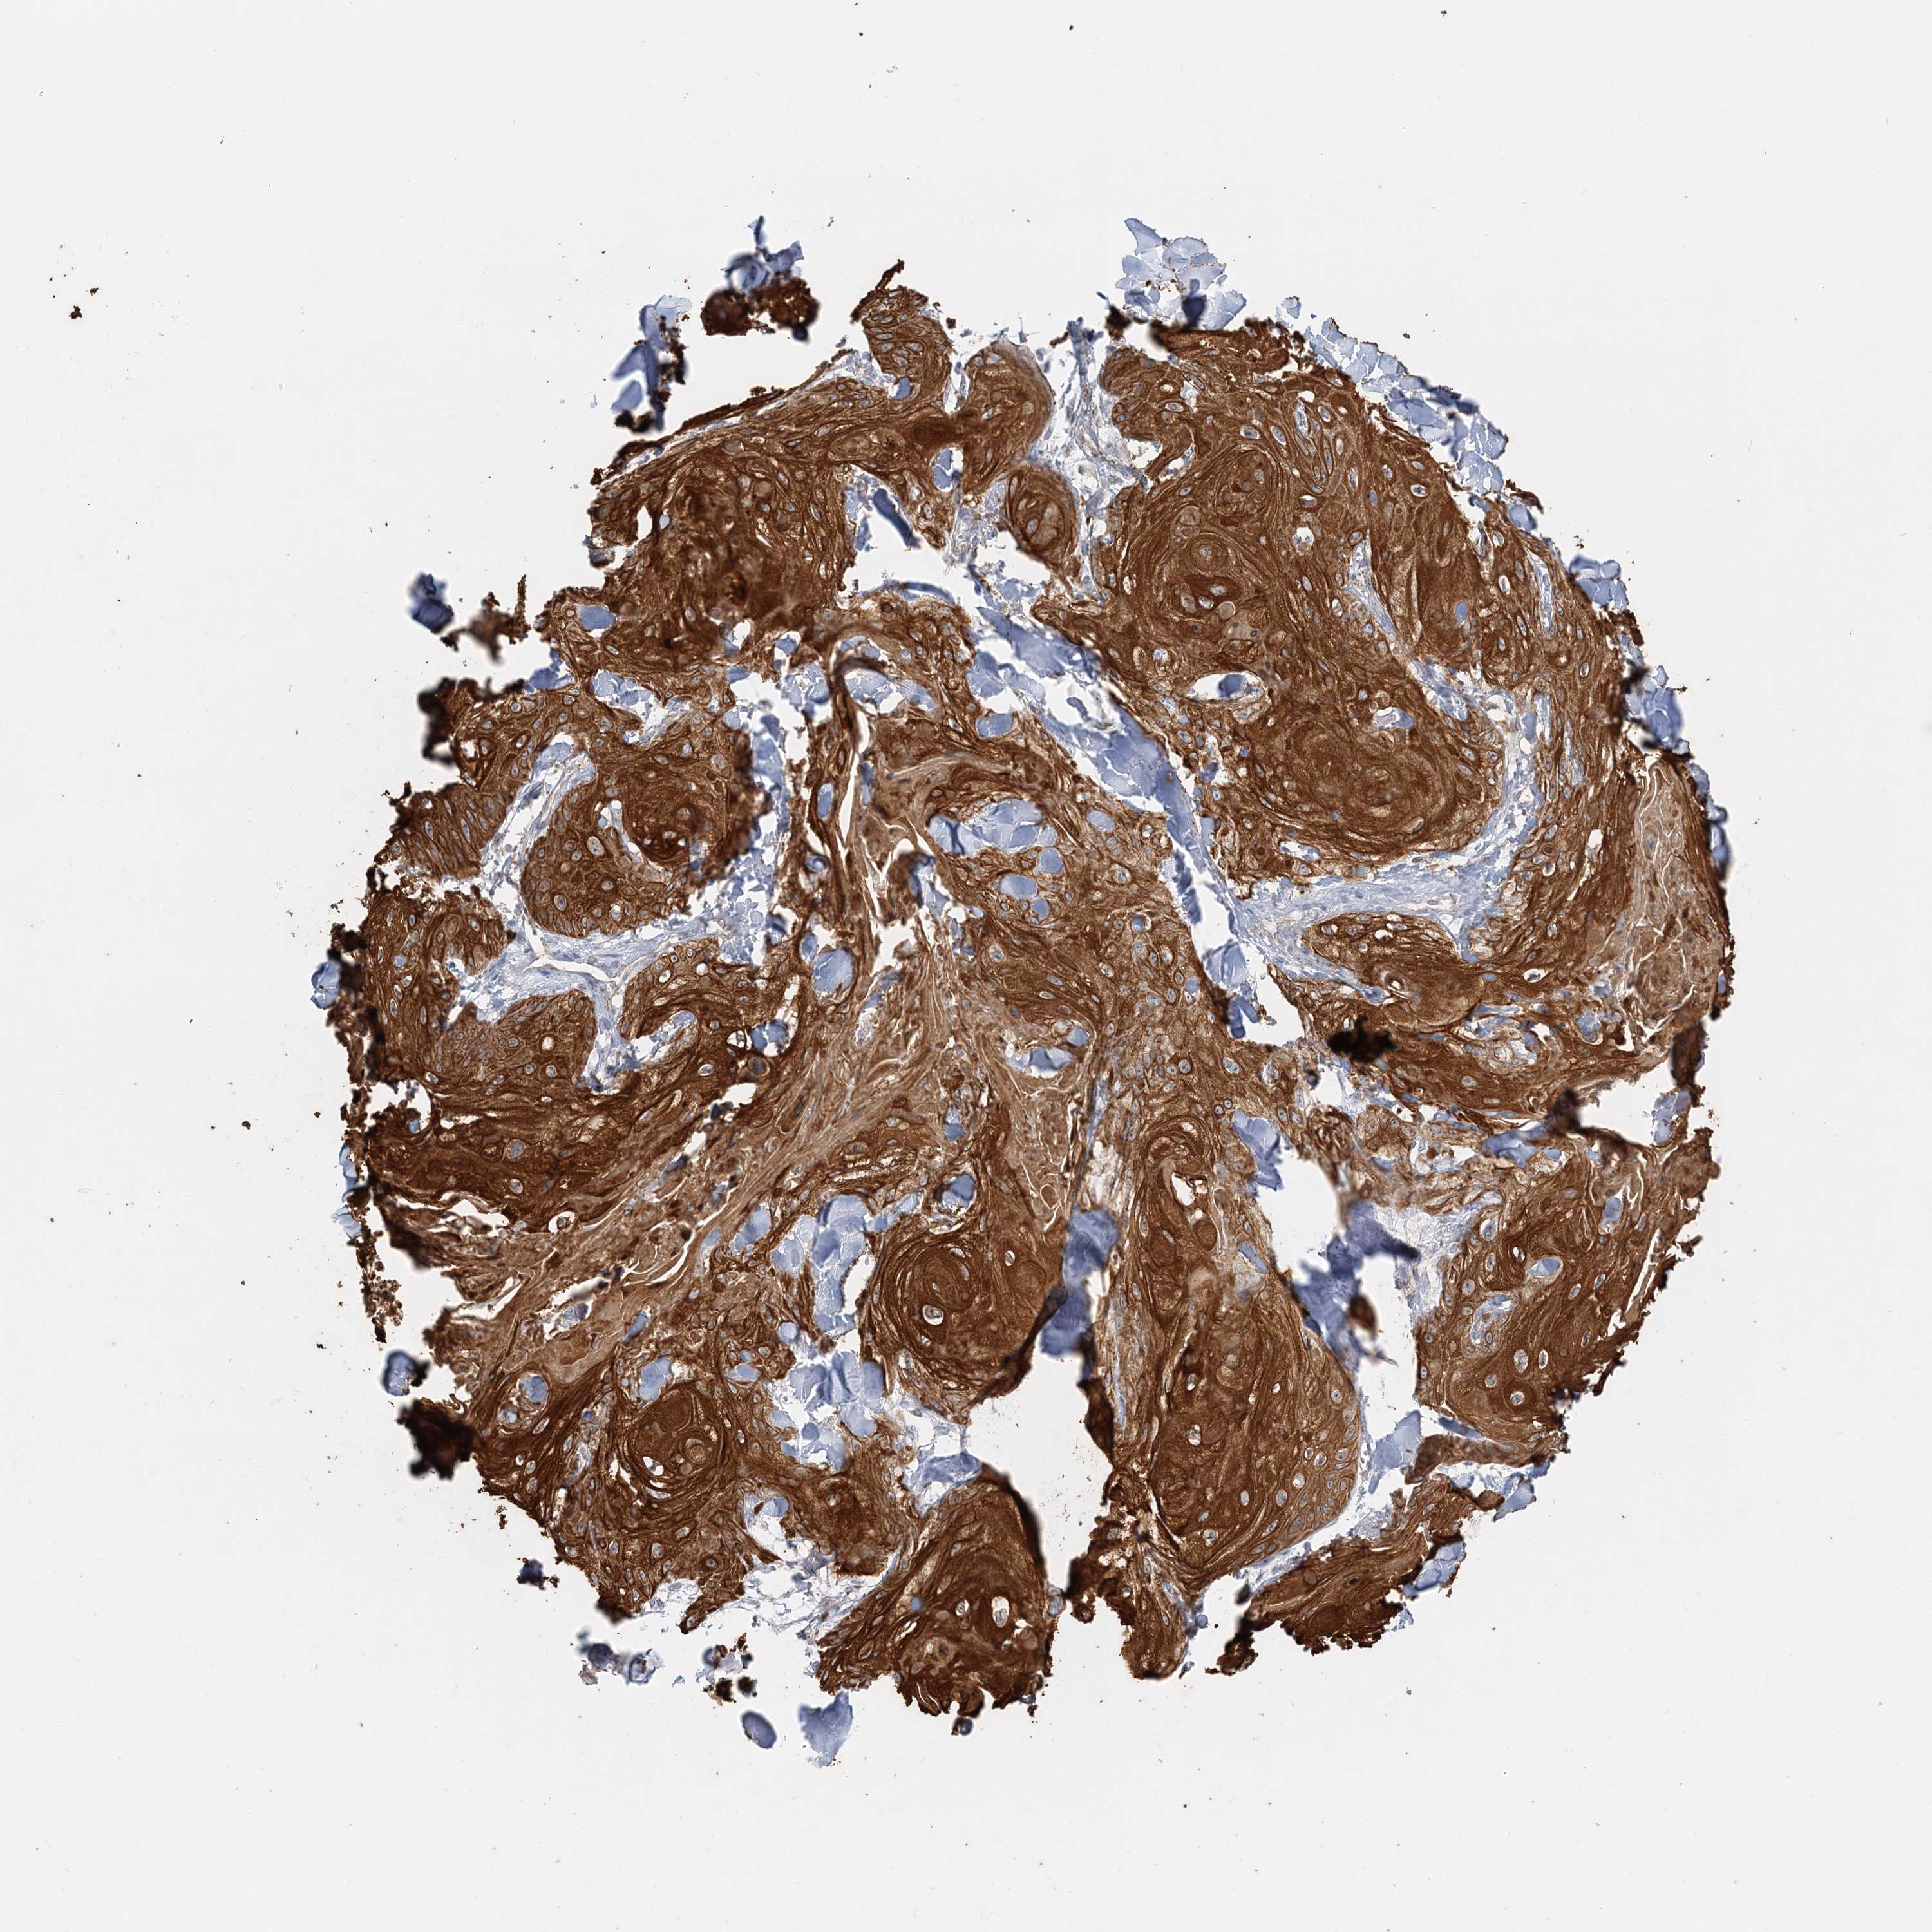

Basal cell and squamous cell cancer

SKIN CANCER - Protein expressioni

A mouse-over function shows sample information and annotation data. Click on an image to view it in a full screen mode. Samples can be filtered based on level of antibody staining by selecting one or several of the following categories: high, medium, low and not detected. The assay and annotation is described here.

Antibody stainingi

Antibody staining in the annotated cell types in the current human tissue is reported as not detected, low, medium, or high, based on conventional immunohistochemistry profiling in selected tissues. This score is based on the combination of the staining intensity and fraction of stained cells.

Each image is clickable and will lead to virtual microscopy that enables deeper exploration of all samples and also displays staining intensity scores, fraction scores and subcellular localization as well as patient and tissue information for each sample.

Antibody HPA036805

Antibody HPA036806

Staining

High

Strong

>75%

Cytoplasmic/membranous

Squamous cell carcinoma, metastatic, NOS